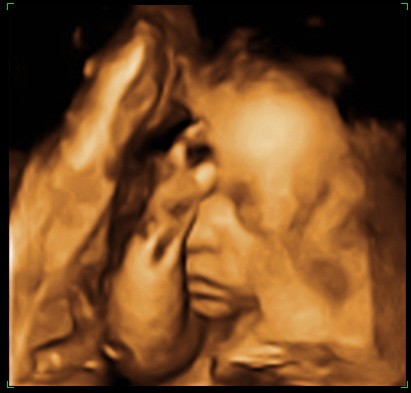

... Wrzucam zdjęcia z ubiegłej środy, czyli 28 tydzień z hakiem.